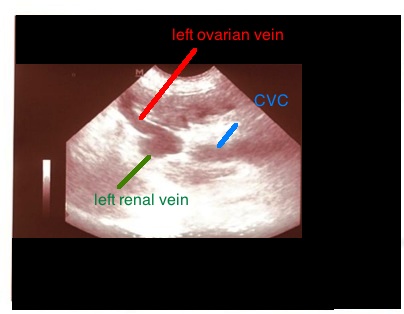

Η πυλαία κυκλοφορία μπορεί να επηρεαστεί από προ-ηπατικά ( συμπίεση της πυλαίας από κάποια μάζα), ηπατικά (φλεγμονή του ήπατος ή κίρρωση του οργάνου) και μετα-ηπατικά ( δεξιά καρδιακή ανεπάρκεια) αίτια. Σε αυτές τις περιπτώσεις η ροή στην πυλαία φλέβα διαταράσσεται, η ταχύτητα μειώνεται και η κυματομορφή Doppler αλλοιώνεται. Επίσης τα αγγεία, όπως η σπληνική φλέβα και η πρόσθια μεσεντέρια φλέβα, διατείνονται και μπορεί να έχουν οφιοειδή πορεία. Σε χρόνιες καταστάσεις, για να αποσυμφορηθεί η πυλαία κυκλοφορία, επανακινητοποιούνται παράπλευρα δίκτυα τα οποία είχαν υποπλαστεί, λόγω αλλαγής των πιέσεων στο αγγειακό δίκτυο μετά την εμβρυϊκή ζωή. Ένα παράπλευρο δίκτυο κινητοποιείται συχνά για τη συλλογή του αίματος από το δίκτυο της οπίσθιας μεσεντέριας φλέβας μέσω της αριστερής ωοθηκικής φλέβας, η οποία εκβάλλει στην αριστερή νεφρική και από εκεί καταλήγει στην οπίσθια κοίλη φλέβα.

Στην παραπάνω φωτογραφία φαίνεται διάταση της αριστερής ωοθηκικής φλέβας λίγο πριν την εκβολή της στην αριστερή νεφρική φλέβα.